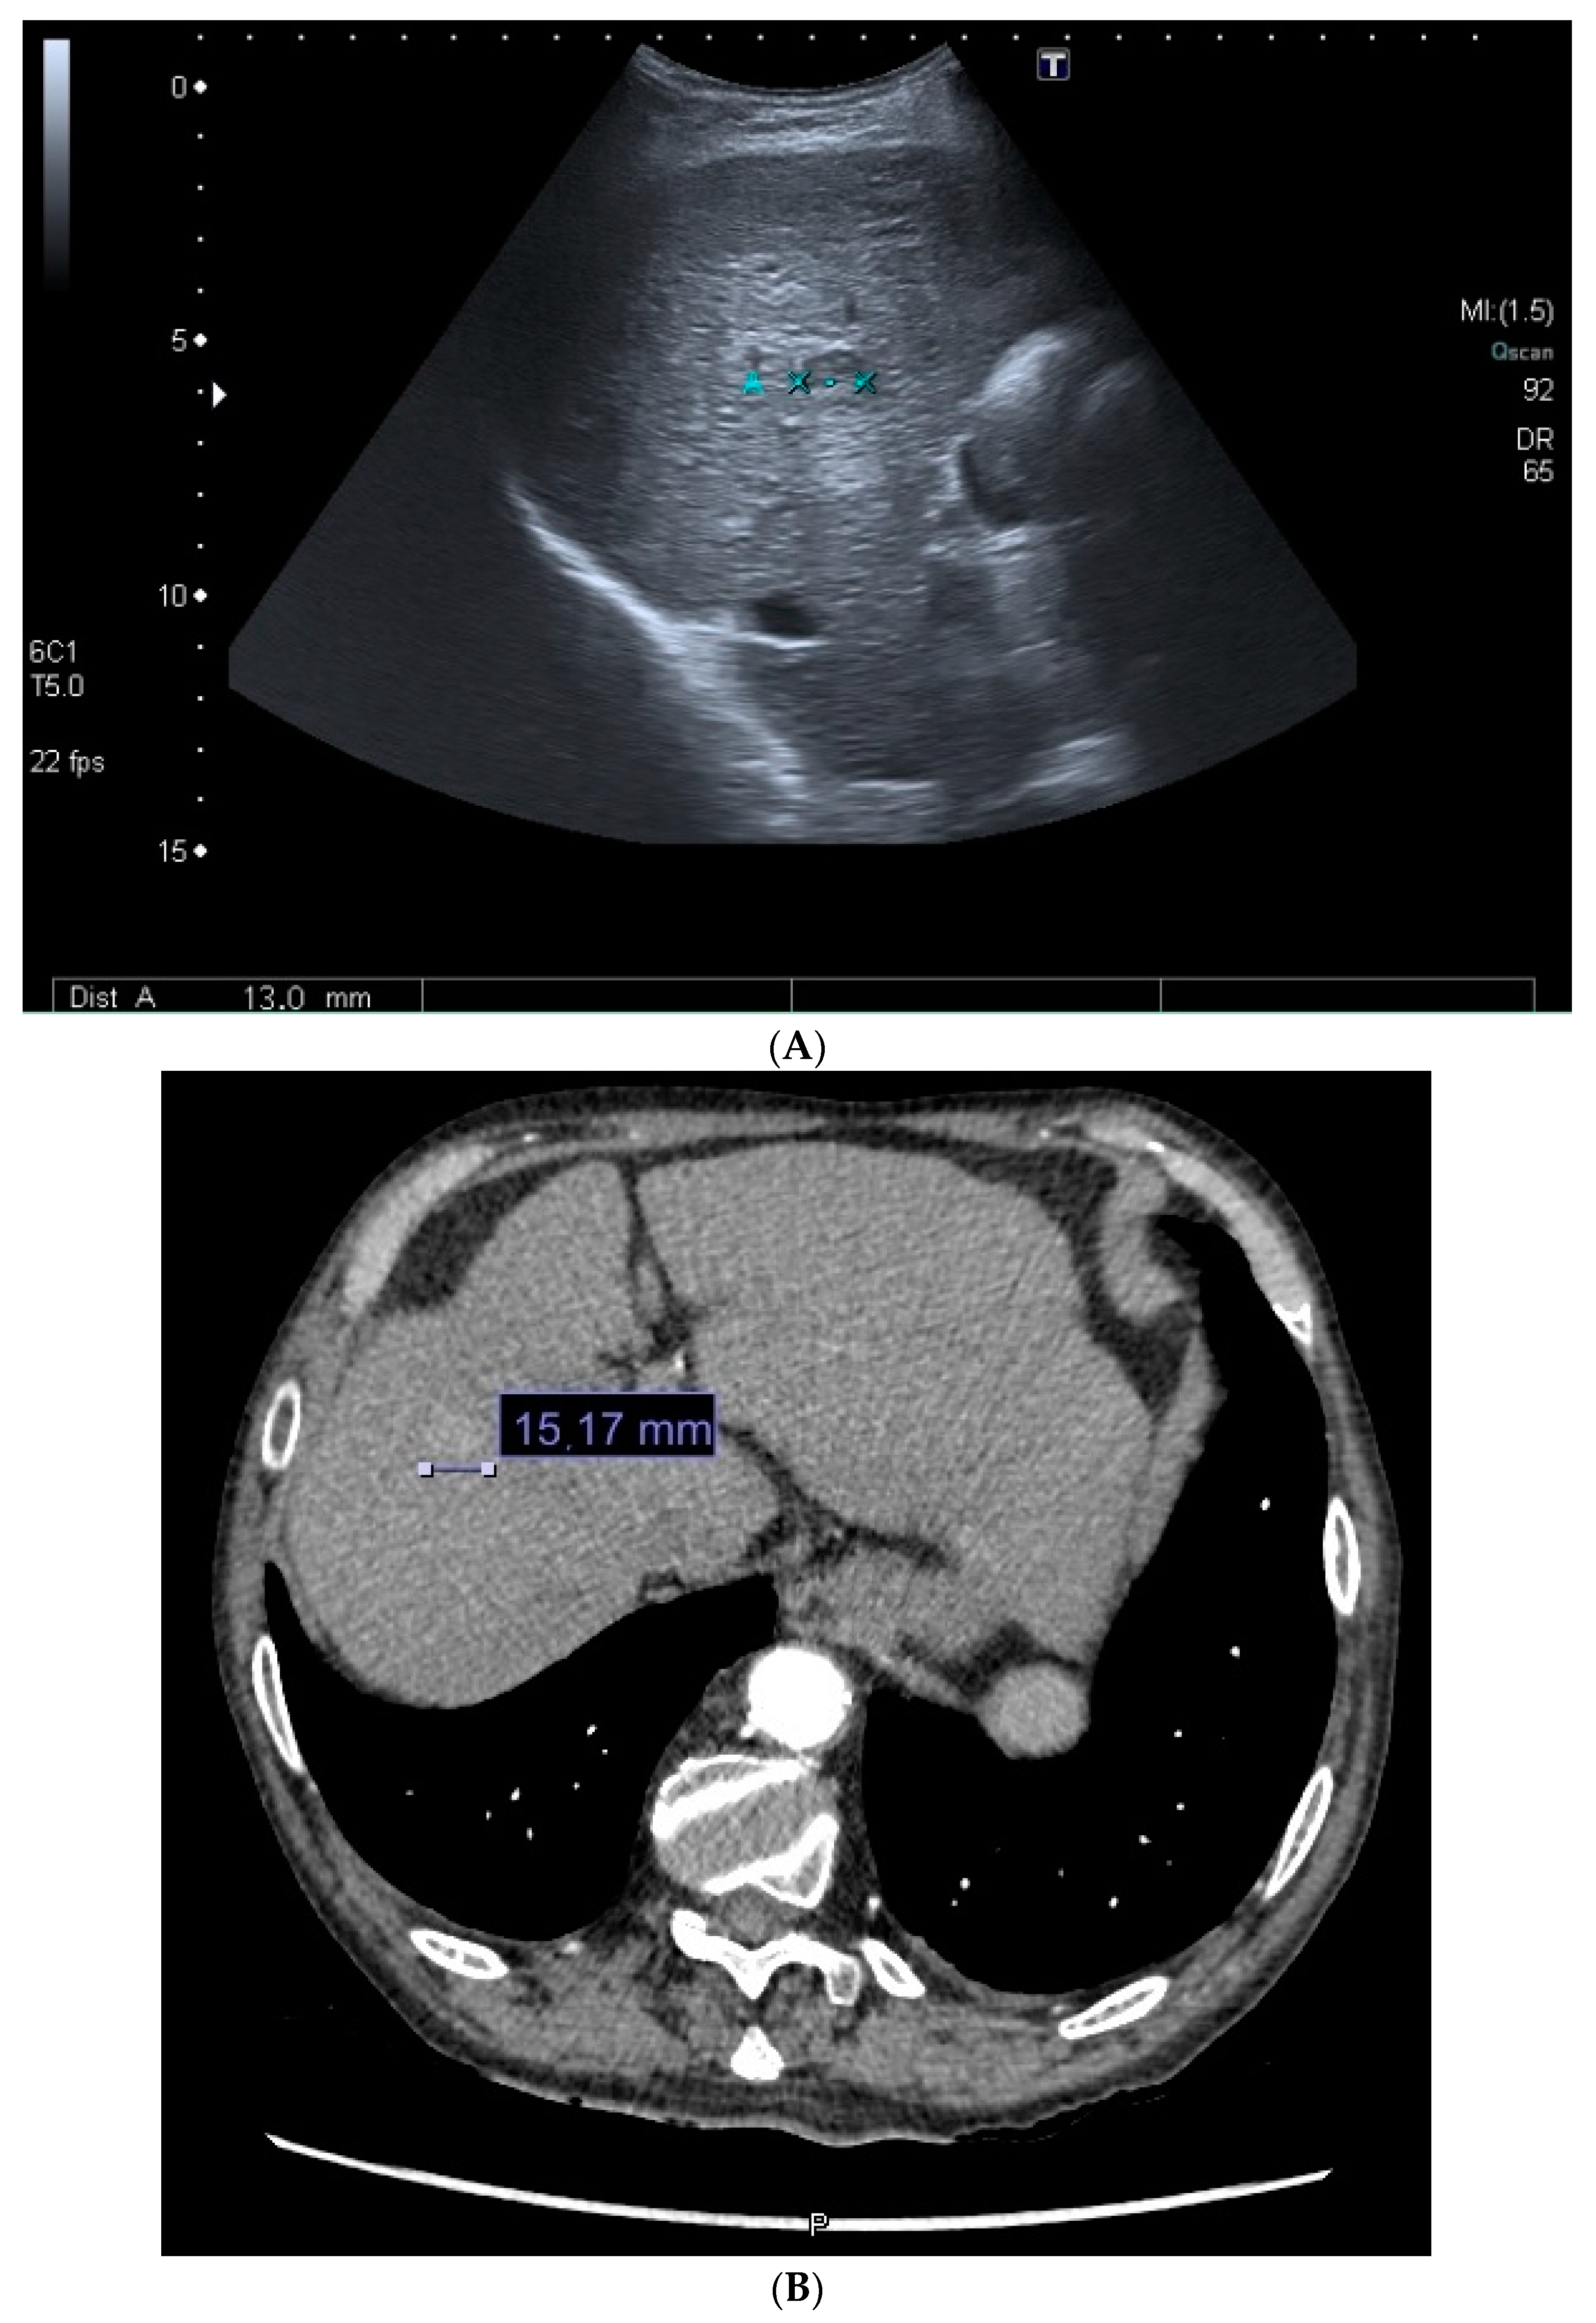

| Diagnostic method | Biopsy | 54 (33.33%) | 16 (55.17%) |

| Imaging test | 108 (66.66%) | 13 (44.87%) | |